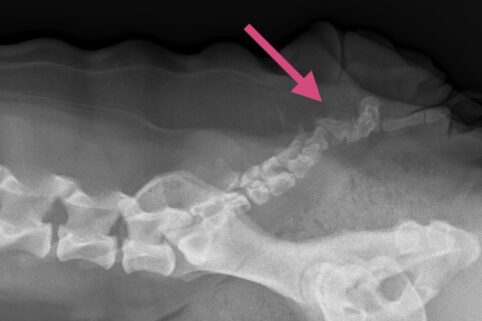

Før operationen tages et røntgenbillede af bagparten, så halehvirvlernes placering kan vurderes.

Der lægges et ovalt snit rundt omkring halens tilhæftning på rumpen. Ud fra røntgenbillederne vurderes halehvirvlernes udformning og ud fra dette besluttes, hvor snittet skal lægges. Det er stort set aldrig muligt at bevare noget af halen.

Huden sys sammen, og der tages et nyt røntgenbillede af halen.